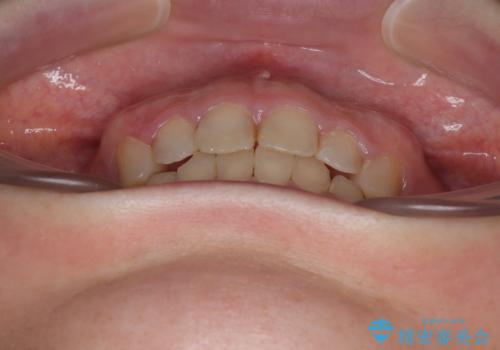

- 上の前歯が出っ歯と突出した口元を気にして来院された患者様です。

上顎歯列全体が前方に飛び出している印象であったので、上顎左右の第一小臼歯2本を抜歯し、ワイヤー装置にて抜歯矯正を行うこととしました。